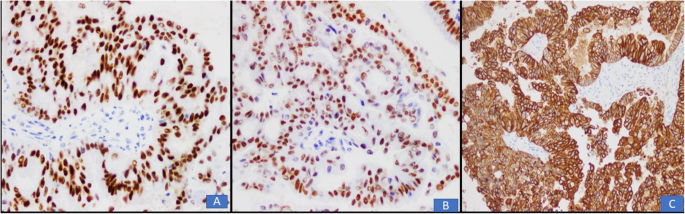

a Picture of an ovarian seromucinous borderline tumour. The

a Picture of an ovarian seromucinous borderline tumour. The capsule is